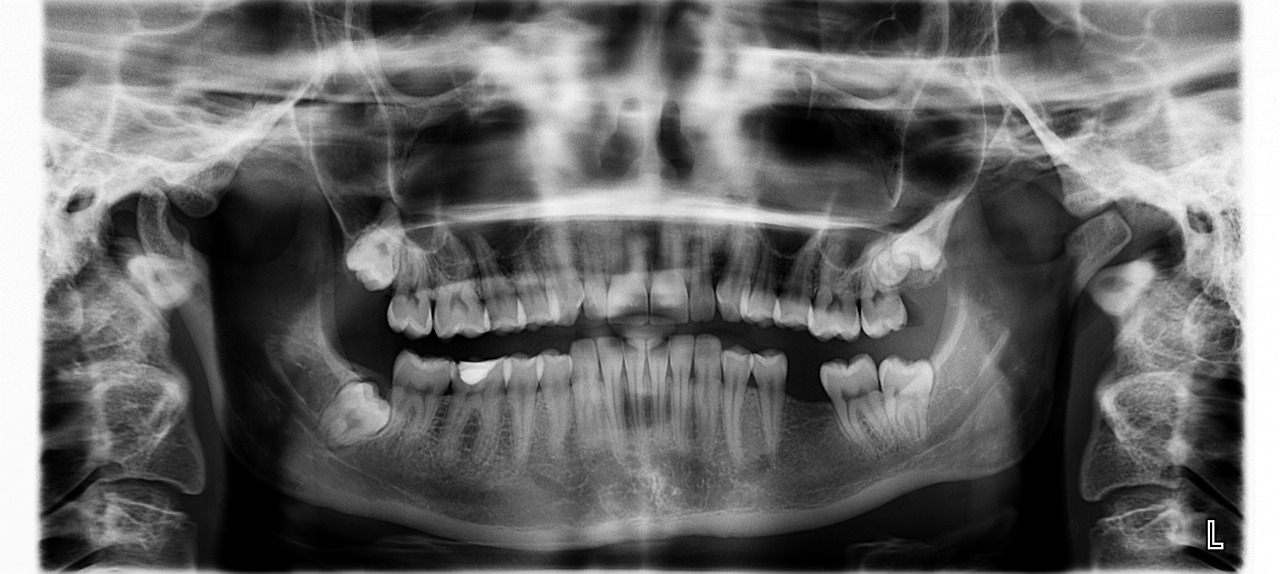

Alalõua esimene molaar

• Lõikub suhu 6. eluaastal

• Hamba juurte areng lõppeb 9.-10. eluaastaks

• Keskmine pikkus 21 mm

Alalõua esimene molaar on suure krooniosaga kahejuureline hammas, mis lõikub jäävhammastest kõige varem. Juuri tähistatakse mesiaalne (M) ja distaalne (D). Mesiaalses juures on tavaliselt 2 juurekanalit, distaalses juures 1-2 juurekanalit. Hamba anatoomia on keeruline, kuna esinevad ka mõned variatsioonid.

Juurekanalite kurvatuurid:

• mesiaalne juur – distaalsele > sirge

• distaalne juur – sirge > distaalsele

Pulbisarved (neid on neli) on suhteliselt väikesed ning pulbiruumi läbilõige on trapetsi-, rombi- või kolmnurgakujuline.

Distaalne (D) juur on ovaalse diameetriga, võib olla pisut lühem mesiaalsest ning selles paikneb enamasti üks lai juurekanal, mis on diameetrilt elliptiline, ovaalne või neerukujuline. Juur on massiivne, enamasti sirge. Tipuosas võib esineda kurvatuur distaalsele, harva ka lingvaalsele. Juur on laiem bukolingvaalselt, väiksema diameetriga mesiodistaalselt. Juurekanal on kogu ulatuses lai ning kitseneb alles mõned millimeetrid enne juure tipuosa. Kui juures paikneb kaks juurekanalit, siis juurekanaleid eraldab tihti dentiinisaareke. Juurekanalid võivad hargneda eraldiseisvateks juurekanaliteks ka alles juure keskosas, samuti võivad eraldi algavad juurekanalid liituda juure tipuosas üheks juurekanaliks.

Mesiaalne (M) juur on kõverusega distaalsele ning diameetrilt trapetsikujuline või ovaalne. Juurekanaleid on kaks – mesiobukaalne (MB) ja mesiolingvaalne (ML). Juurekanalid on tugevate kurvatuuridega, kõveram on mesiobukaalne juurekanal. Mesiaalsed juurekanalid võivad ühineda tipuosas või kulgeda eraldi juuretipuni välja. Juurekanalite vahel paiknevad ohtrad ühendused ehk istmused. Juurekanalid on reeglina kitsad ning diameeter kahaneb juuretipu suunas.  Ristläbilõikes võib  juurekanal olla ümar või ovaalne, kuid ühenduste korral neerukujuline või 8-kujuline.

Anatoomilisteks variatsioonideks on mesiaalses juures esinevad kolm juurekanalit või esineb 2 distaalset juurt (lingvaalne juur väike ja kõveram), kus mõlemas on üks juurekanal.